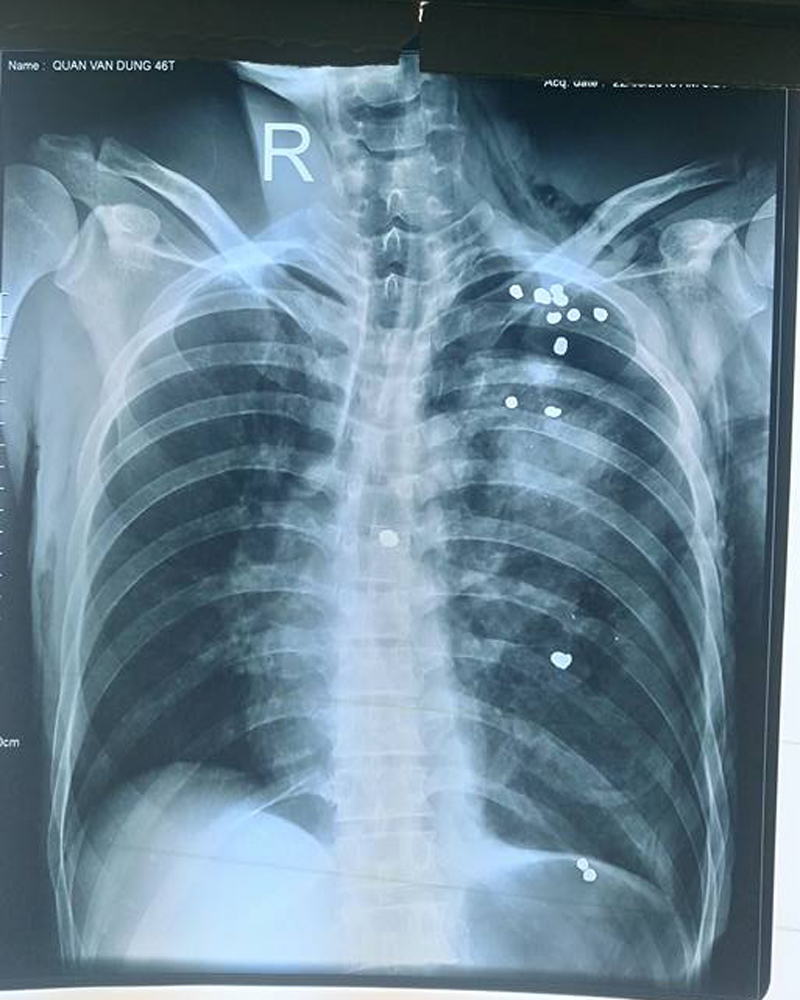

Hình ảnh viên đạn găm khắp lồng ngực, bụng nạn nhân

Bác sỹ CKII Nguyễn Kim Cương, Trưởng khoa Ngoại Tổng hợp, Bệnh viện đa khoa tỉnh Tuyên Quang -Trưởng kíp mổ cho biết, Bệnh nhân bị gần 20 viên đạn găm khắp người, vết thương thấu ngực trái dưới mỏm tim khoảng 3cm, khu liên sườn VI, VII có vết thương nham nhở kích thước khoảng 2cm, xuyên thấu từ thùy giữa lên thùy đỉnh phổi trái.

Sau 2 giờ phẫu thuật, các bác sỹ tiến hành mở ngực, bụng lấy ra rất nhiều dị vật và đạn ra khỏi lồng ngực.